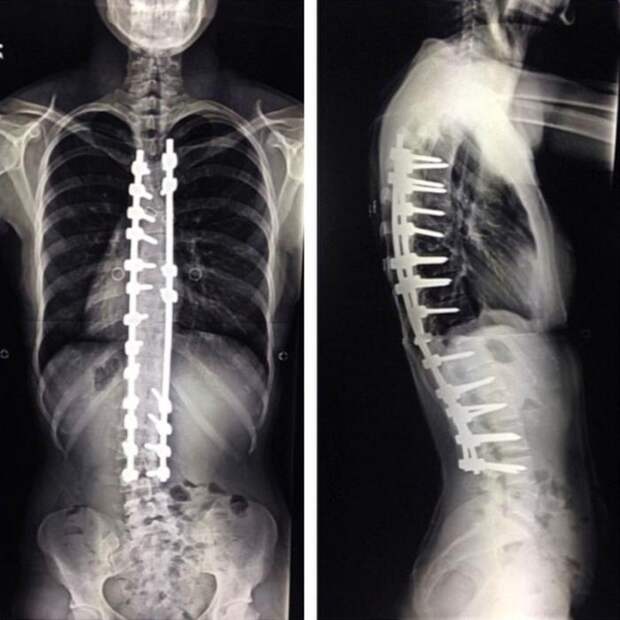

Не всегда подростки перерастают сколиоз, и позвоночник принимает дикую форму. В таких случаях единственное решение проблемы - спондилодез. Это серьезная операция, во время которой смежные позвонки обездвиживаются.

Последствия процедуры очень болезненны - приходится месяцами отходить и пить обезболивающие препараты.

Эта девушка смогла пройти через это тяжелое испытание и теперь живет полной жизнью. Хотя дискомфорт чувствует до сих пор.